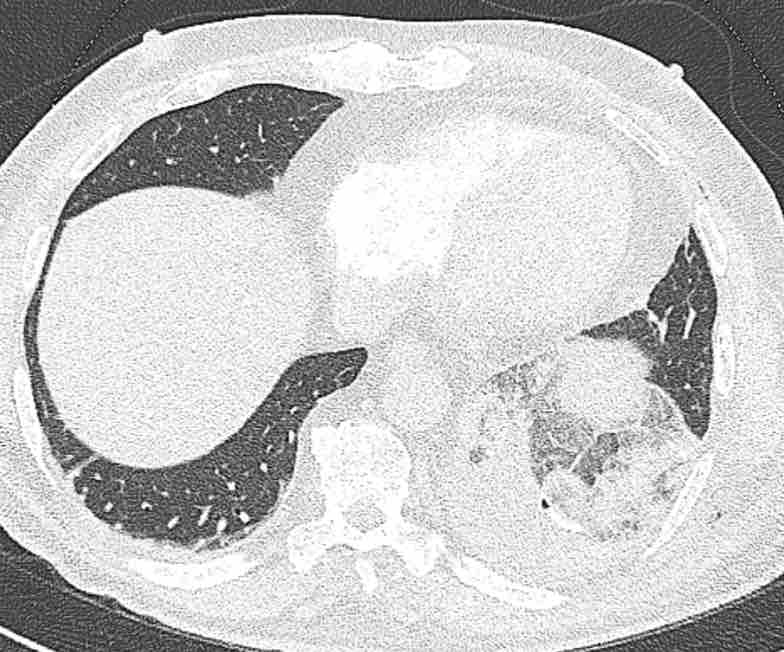

Hình ảnh

Cuộn qua các hình ảnh.

Theo dõi các phế quản của thùy dưới phổi trái cho thấy nhánh phân thùy đầu tiên của thùy dưới phổi trái còn thông; đó là phế quản phân thùy đỉnh.

Các ghim phẫu thuật nằm tại vị trí của các phân thùy đáy sau và đáy bên (LB9/10), vốn thường được cắt bỏ cùng nhau.

Do đó, phân thùy phổi có hình ảnh kính mờ và đông đặc phải là phân thùy đáy trước của thùy dưới phổi trái (LB8).

Động mạch phổi đến phân thùy này cũng không ngấm thuốc cản quang, và bản đồ tưới máu iốt nhấn mạnh thêm tình trạng nhồi máu.

Bệnh nhân đã được phẫu thuật lại và tiến hành cắt bỏ phân thùy bị nhồi máu, với xác nhận qua giải phẫu bệnh.

Trên bản đồ tưới máu iốt, có sự tưới máu ở thùy trên phổi trái và phân thùy đỉnh của thùy dưới phổi trái, nhưng không có sự tưới máu ở phân thùy đáy trước của thùy dưới phổi trái.